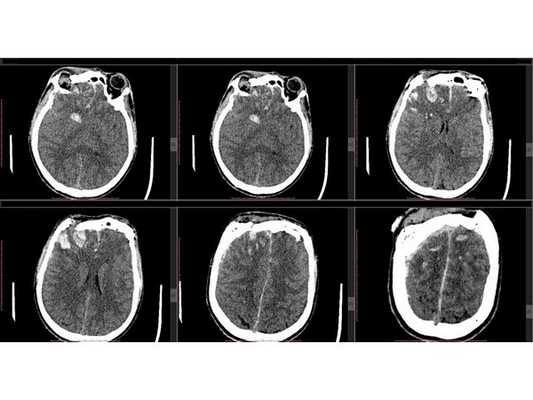

КТ головного мозга: оскольчатый вдавленный перелом лобной кости, линейный перелом ската затылочной кости, а также перелом лицевого отдела черепа III степени по Le Fort с остаточной деформацией стенок; множественные ушибы и отёк вещества головного мозга лобных долей; скопление крови в пазухах носа. КТ шейного и поясничного отделов позвоночника: травм и патологий нет. КТ грудной клетки и грудного отдела позвоночника: ушиб правого лёгкого. Офтальмологический осмотр: контузия правого глазного яблока тяжёлой степени, скопление крови между сетчаткой и пигментным эпителием левого глаза.

Сочетанная черепно-челюстно-лицевая травма. Открытая проникающая черепно-мозговая травма. Ушиб головного мозга тяжёлой степени с преимущественным поражением лобных долей и формированием очагов размозжения в полюсно-базальных отделах. Многооскольчатый вдавленный перелом лобной кости, переходящий на основание черепа. Перелом лицевого отдела черепа III степени по Le Fort с деформацией стенок правой глазницы. Ушиб правого глаза тяжёлой степени, субретинальное кровоизлияние левого глаза.

Необходимо выполнить трепанацию черепа в лобной области; удалить, сопоставить и зафиксировать вдавленные костные фрагменты при помощи минипластин; удалить внутримозговую гематому; восстановить форму свода черепа с использованием металлической пластины. Ход операции: ⠀•⠀выполнен разрез мягких тканей в лобной области по Зуттеру, гемостаз моно- и биполярной коагуляцией по ходу скелетирования кости до уровня надбровных дуг, кожно-апоневротический лоскут откинут базально; ⠀•⠀открыт доступ к вдавленным костным фрагментам, в правой надглазничной области имеется повреждение костных фрагментов твёрдой мозговой оболочки и головного мозга, виден мозговой детрит (размозжённая мозговая ткань); ⠀•⠀с помощью краниотома костные фрагменты мобилизованы и удалены из раны, визуализировано повреждение твёрдой мозговой оболочки в области правой лобной доли; ⠀•⠀плотные сгустки крови и мозговой детрит аспирированы, отмыты физраствором и удалены, объём мозгового детрита — примерно 30 мл; ⠀•⠀произведён гемостаз с использованием биполярной электрокоагуляции, перекиси водорода и воска, твёрдая мозговая оболочка ушита и подшита по периметру костного дефекта нитью Викрил; ⠀•⠀самый крупный фрагмент кости уложен на место, костный дефект закрыт металлической пластиной; ⠀•⠀все костные фрагменты и сетчатая пластина фиксированы 10 винтами 1,5*5,0 мм и 2 минипластинами, операционная рана ушита послойно, кожа ушита непрерывным швом по Мультановскому, наложена асептическая повязка.

Сознание пациента восстановилось до 15 баллов по шкале комы Глазго (т. е. до ясного), но имелись остаточные когнитивно-мнестические нарушения. Менингеальные симптомы регрессировали. Операционная рана зажила первичным натяжением, швы сняты. По результатам контрольной КТ головного мозга отмечена положительная динамика. С целью исключения возможного менингита в послеоперационном периоде пациенту выполнена диагностическая люмбальная пункция и анализ спинномозговой жидкости: ликвор светло-красного цвета, мутный, цитоз — 10 в 1 мкл, общий белок — 0,7 г/л, глюкоза — 2,64 мМоль/л, эритроциты — 20-30 в п/зр, свежие. Заключение: данных за менингит нет.